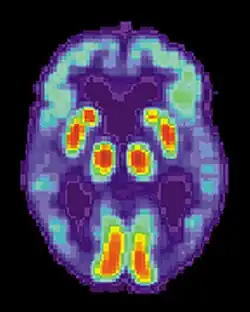

Maladie d'Alzheimer

La maladie d'Alzheimer (MA) est une maladie cérébrale progressive, dégénérative et fatale, dans laquelle est recensée une perte importante des cellules. Par conséquent, la mort des cellules cérébrales survient, bien que cette maladie soit la forme de démence la plus répandue[10]. À travers le monde, il existe 1 à 5 % de la population atteinte de la maladie d'Alzheimer[11]. Il est estimé que 500 000 Canadiens souffrent actuellement de la maladie d'Alzheimer ou d'une autre démence liée. Elle est la cause de handicap la plus répandue chez les individus âgés de 65 ans ou plus[10]. Les femmes sont disproportionnellement atteintes par cette maladie[12].